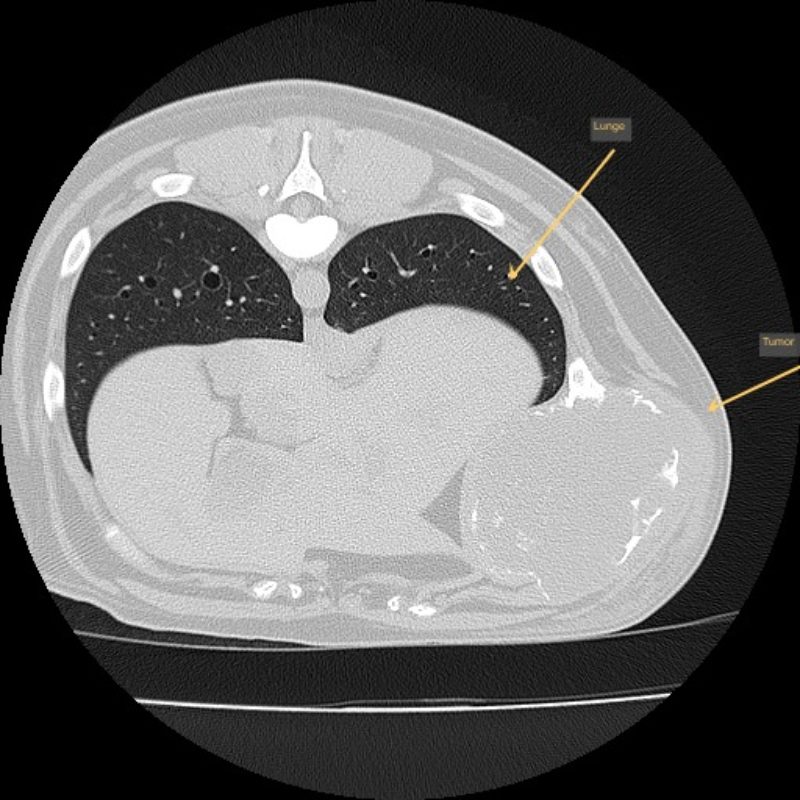

Leo wurde nun nach einer gründlichen allgemeinmedizinischen sowie labortechnischen Untersuchung zur Computertomographie (CT) angemeldet, die in Vollnarkose stattfinden muss. Mit dieser Technik werden mit Hilfe von Röntgenstrahlen ein Millimeter dünne Schichtaufnahmen angefertigt und damit das genaue Ausmaß des Tumors dargestellt. Zum anderen kann im Vergleich zu einem konventionellen Röntgenbild eine überlagerungsfreie Aussage über den Zustand des benachbarten Weichteilgewebes getroffen werden. Diese Informationen sind für den Chirurgen unumgänglich, damit er die Operation planen kann.

In diesem Fall wurde durch die CT das enorme Ausmaß der Umfangsvermehrung deutlich, sodass insgesamt drei Rippen inklusive der dazwischenliegenden Muskeln in Mitleidenschaft gezogen wurden. Die gute Nachricht war, dass der innerhalb der Bauchhöhle unmittelbar anliegende linke Leberlappen, Magen und Milz sowie der hintere Anteil des linken Lungenflügels im Brustkorb noch nicht vom Tumorwachstum erfasst waren.

Um eine Aussage für die Prognose hinsichtlich der Überlebenszeit des Patienten treffen zu können, die sich bei bösartigen Tumoren hauptsächlich vom Vorhandensein von Metastasen ergibt, wurde in der gleichen CT-Untersuchung die Brust- und Bauchhöhle von Leo mitgescannt. In der Lunge, den dem Tumor benachbarten Lymphknoten, sowie Leber und Milz setzen sich erfahrungsgemäß die frühesten Metastasen fest. Manche Besitzer wollen ihrem Liebling bei fortgeschrittener Tumorstreuung die Operation und etwaige langwierige Nachsorgebehandlungen ersparen. Bei diesem Patienten, der ja insgesamt in hervorragender körperlicher Verfassung war, konnten wir weder in der Brust- noch in der Bauchhöhle Metastasen feststellen, sodass einer operativen Entfernung des bösartigen Tumors nichts mehr im Wege stand.